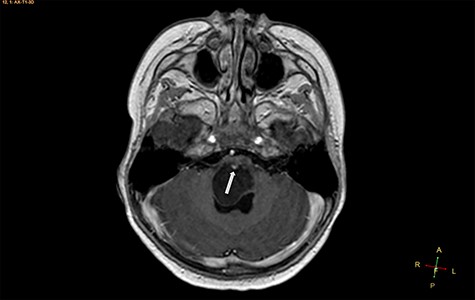

Axial T1-weighted image, with contrast agent, revealing a cystic mass, with a very small enhancing mural nodule (arrow).

A 3-year-old male, who suffered from a sudden, tonic–clonic seizure, followed by a short period of unconsciousness, was instantly transported to Children’s Hospital 2. The patient’s medical history was normal. No neurological deficits were detected during the clinical assessment, and laboratory tests and electroencephalography were within acceptable ranges. The clinician performed a brain magnetic resonance imaging (MRI) scan, with contrast agent. No lesions were recognized in the supratentorial structures. A clear boundary cystic mass (27 × 25 × 26 mm3) was located in the medulla oblongata, without perilesional vasogenic edema. Hydrocephalus was not observed. The signal intensity of the mass was low on the sagittal T1-weighted image (Fig. 1) and high on the axial T2-weighted image (Fig. 2). On coronal fluid-attenuated inversion recovery imaging, the mass was isointense relative to the parenchyma, but the intensity was higher than that of cerebrospinal fluid (CSF, Fig. 3). On susceptibility-weighted imaging, no indicators of hemorrhage or ossification were observed within the mass. The mass was partially hyperintense on diffusion-weighted imaging (DWI) and slightly hypointense on the apparent diffusion coefficient (ADC) map. The mean ADC values of the parenchyma, mass and CSF were 0.71, 1.3 and 1.59 × 10−3 mm2/s, respectively (Fig. 4). On T1-weighted imaging, with contrast enhancement, the thin wall of the mass was very slightly enhanced, and we observed a tiny nodule inside the mass that was strongly enhanced (Fig. 5). With a provisional diagnosis of pilocytic astrocytoma, the patient underwent surgery to completely eradicate the tumor. Eventually, the histopathological result revealed a typical EC (Fig. 6). The postoperative period was uneventful, and the patient was discharged after 2 weeks.

Histopathologically, the ECs are filled with protein, keratin and cholesterol. The cyst wall is typically covered with stratified, squamous epithelia, with the outward backing of collagen [3–8]. The appearance on MRI is heavily dependent on the chemical architecture of these intracystic components. The hypointensity observed on T1-weighted images is associated with the crystalline cholesterol pattern, whereas the hyperintensity on T2-weighted images is induced by the keratinaceous element. Occasionally, ECs appear hyperintense on T1-weighted images and hypointense on T2-weighted images, and these are referred to as white ECs [8, 9]. This specific appearance is caused by unusually high proteinaceous concentrations in the cyst. Typically, ECs do not absorb contrast agent vividly. Approximately 35% of ECs are estimated to enhance slightly and peripherally [9]. DWI is the most useful weapon that can be deployed to recognize ECs. When contrasted with the CSF, because of the superior keratinaceous and proteinaceous concentrations and the relatively little aqueous content, ECs generally appear considerably hyperintense on DWI and hypointense on ADC [9, 10].

Although some recommended imaging characteristics exist for ECs, these characteristics are not always persistent or specific [8–10]. Especially in cases of intraparenchymal ECs, provisional diagnosis can be very difficult due to similarities between EC characteristics and those of other brain neoplasms, including glioma [3–10]. In our case, we identified a medulla oblongata mass in a 3-year-old patient, with a lesion ADC of 1.3 × 10−3 mm2/s, and the identification of an enhanced mural nodule in a cystic lesion resulted in the misdiagnosis of pilocytic astrocytoma, a very common, benign, posterior fossa tumor found in children. According to Kannan et al. [10], unlike extra-axial ECs, intraparenchymal ECs do not often exhibit distinctly limited diffusivity.

In summary, infratentorial, intraparenchymal ECs are exceptionally uncommon in the general population and are even rarer in the pediatric population. In the present report, an unusual presentation of a pediatric EC in the medulla oblongata, with atypical characteristics on DWI and T1-weighted imaging with contrast enhancement, resulted in the misdiagnosis of pilocytic astrocytoma. Neuroradiologists should consider that EC can appear with atypical imaging characteristics, which might imitate glioma; therefore, EC should be included in the differential diagnosis, to obtain better treatment strategies and prognosis.